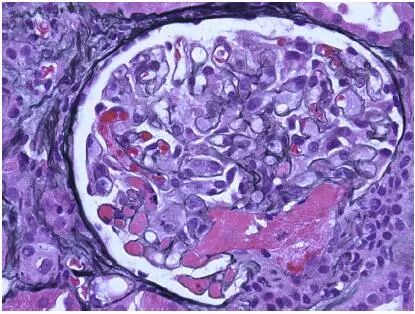

图2 CNI肾毒性TMA,肾小球毛细血管袢和血管极(Jones 银染)

CNI肾毒性导致的血管收缩无形态学变化。急性CNI肾毒性特征包括:近端肾小管上皮细胞空泡化,大小一致;血管损伤,平滑肌细胞丢失;肌细胞胞浆空泡化;细胞坏死或凋亡退化。肌细胞损伤最终发展为局灶性结节性玻璃样变和透明样变,可延伸至小动脉和动脉血管壁整个中层。CNI肾毒性还可引起血栓性微血管病变(TMA),主要累及小动脉和肾小球毛细血管袢。慢性CNI毒性特征为:条状间质纤维化,肾小管萎缩。

近端肾小管上皮细胞空泡化,大小相等,内质网扩张,大型溶酶体。动脉中层和外膜透明质酸积聚。TMA患者可出现肾小球内皮细胞肿胀,内层扩张和肾小球系膜溶解。